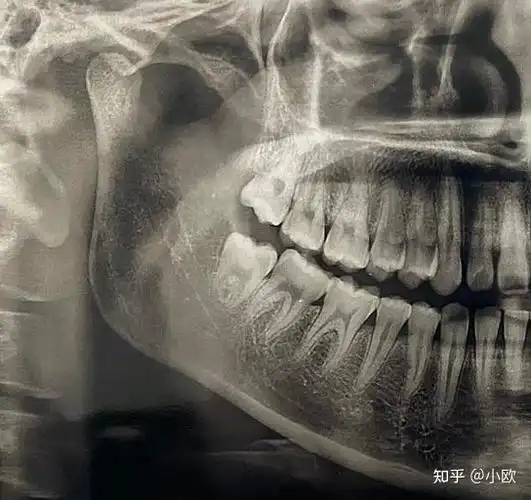

什么样的智齿不用拔